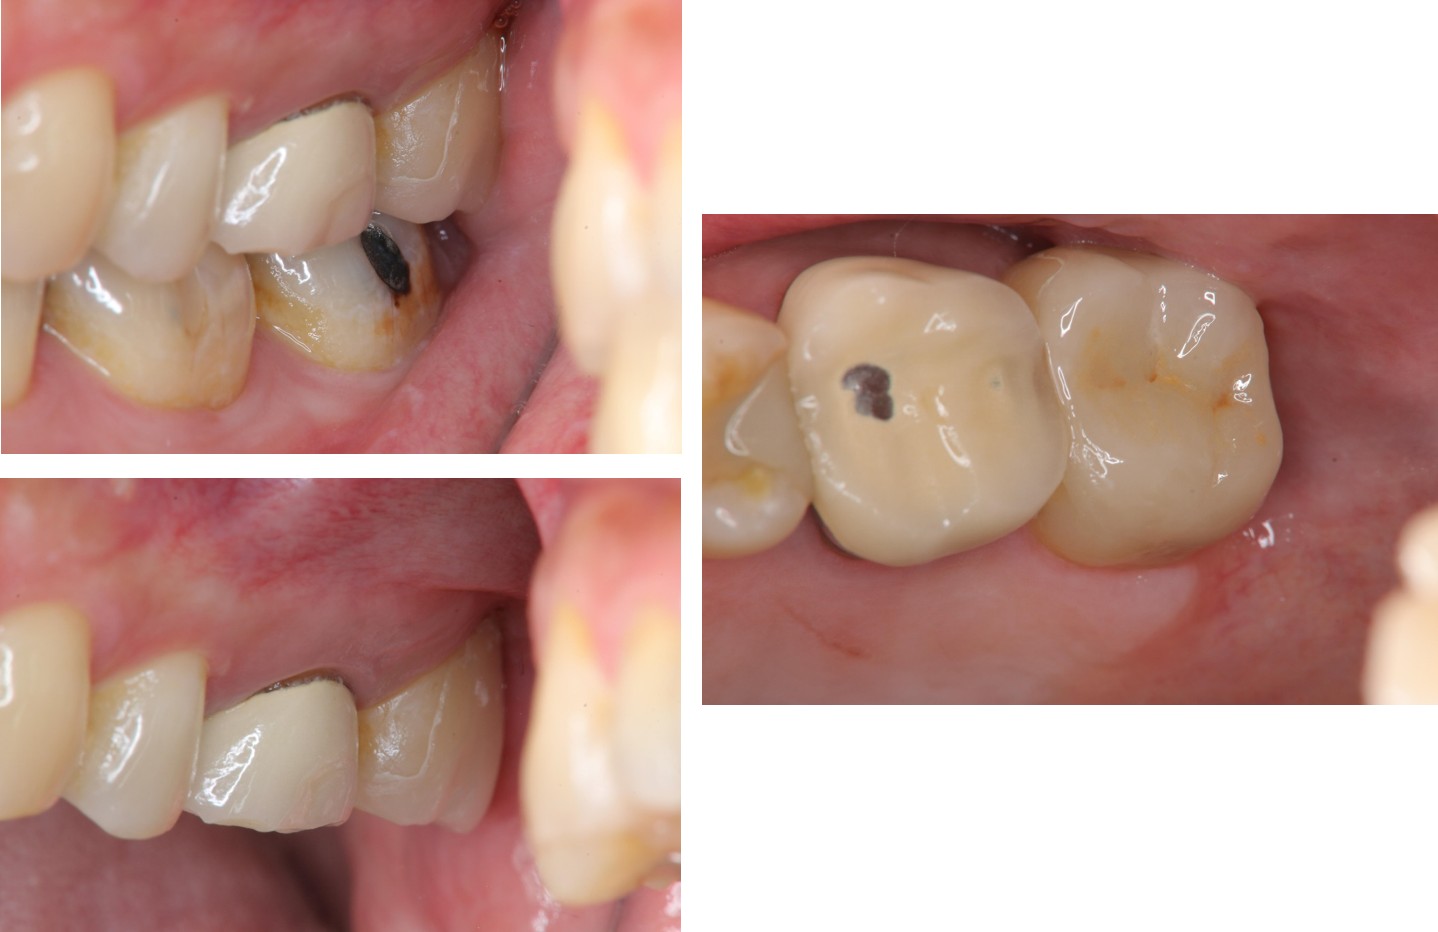

治療前,頰側牙齒蛀牙

治療後口內照

術前、術後比較